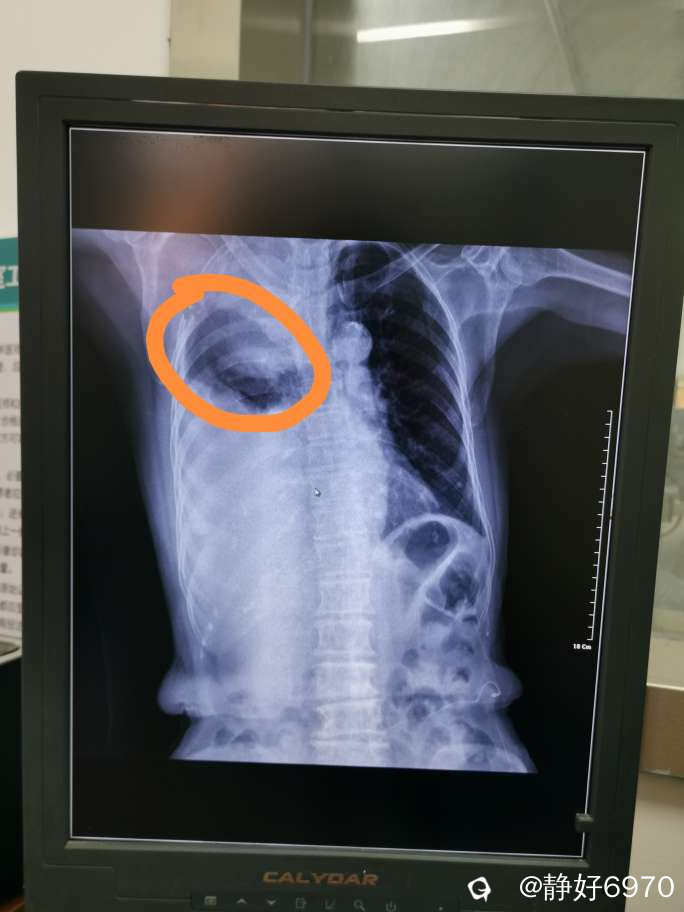

母亲说她胸口疼,手臂也感觉很痛,放射性痛。马上赶到医院给她挂胸痛急诊,两个小时过去了,医生告诉我要马上住院,立刻开车把母亲送到桂林,当时在全州就知道是恶性肿瘤,本来预约了肿瘤科,怕肿瘤两个字把母亲吓倒,换成呼吸科。这是母亲第一次住院。

其实我们都知道母亲是肺癌晚期,是不治之症,存活时间已经是倒计时,我们唯一能做的就是让她在生命的最后时光开开心心过好每一天……足矣!

时间一晃就来到11月,母亲感觉越来越疼痛,连呼吸都困难,于是帮母亲买来制氧机,但是母亲求生欲望还很强烈,还想去医院做理疗,下不了楼老公就背下楼。最后一次带着母亲来到医院,同学亲自帮母亲做检查,发现母亲的胸腔已经充满了积液……难过!